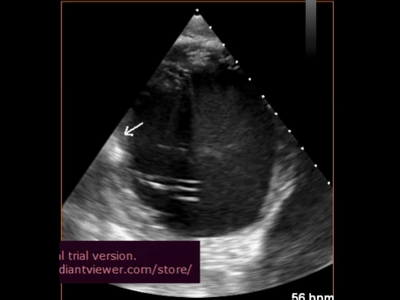

術(shù)中超聲影像

經(jīng)導(dǎo)管心內(nèi)膜注射系統(tǒng):心內(nèi)膜注射系統(tǒng)可保證海藻酸鹽水凝膠被順利植入心臟,發(fā)揮治療作用。其經(jīng)股動(dòng)脈入路,通過DSA(數(shù)字減影血管造影)與TEE(經(jīng)食道超聲心動(dòng)圖)雙重導(dǎo)航定位,確保水凝膠安全且有效地遞送。通過造影劑和超聲雙重確認(rèn)注射針是否刺進(jìn)心室壁且避開血管。植入后,在注射點(diǎn)區(qū)域,通過TEE可見強(qiáng)化回聲。